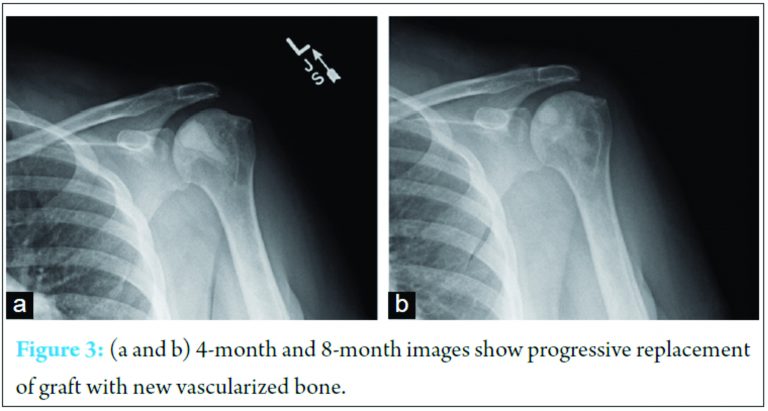

The arthroscope is critical in this stage to allow complete extraction of necrotic subchondral bone while ensuring no penetration of the cartilage. After full decompression was performed, synthetic bone graft (PRO-DENSE, Wright Medical) was injected under fluoroscopy and direct visualization. Given the immediate structural integrity of the graft, maximal removal of necrotic segments was attempted. Care was taken under fluoroscopic guidance not to penetrate the articular surface and no cartilaginous defects were encountered. For both procedures, the standard sickle cell protocol was followed with overnight admission for intravenous hydration followed by discharge with 2 weeks of deep venous thrombosis (DVT) chemoprophylaxis. She was allowed activity as tolerated and physical therapy initiated 2 weeks after each surgery. At 8-month follow-up from the index procedure, she is asymptomatic with a full range of motion on the first shoulder and some mild residual stiffness in the second shoulder (4-month follow-up). Radiographs demonstrate incorporation of the bone graft without evidence of joint collapse or further AVN (Fig. 3).